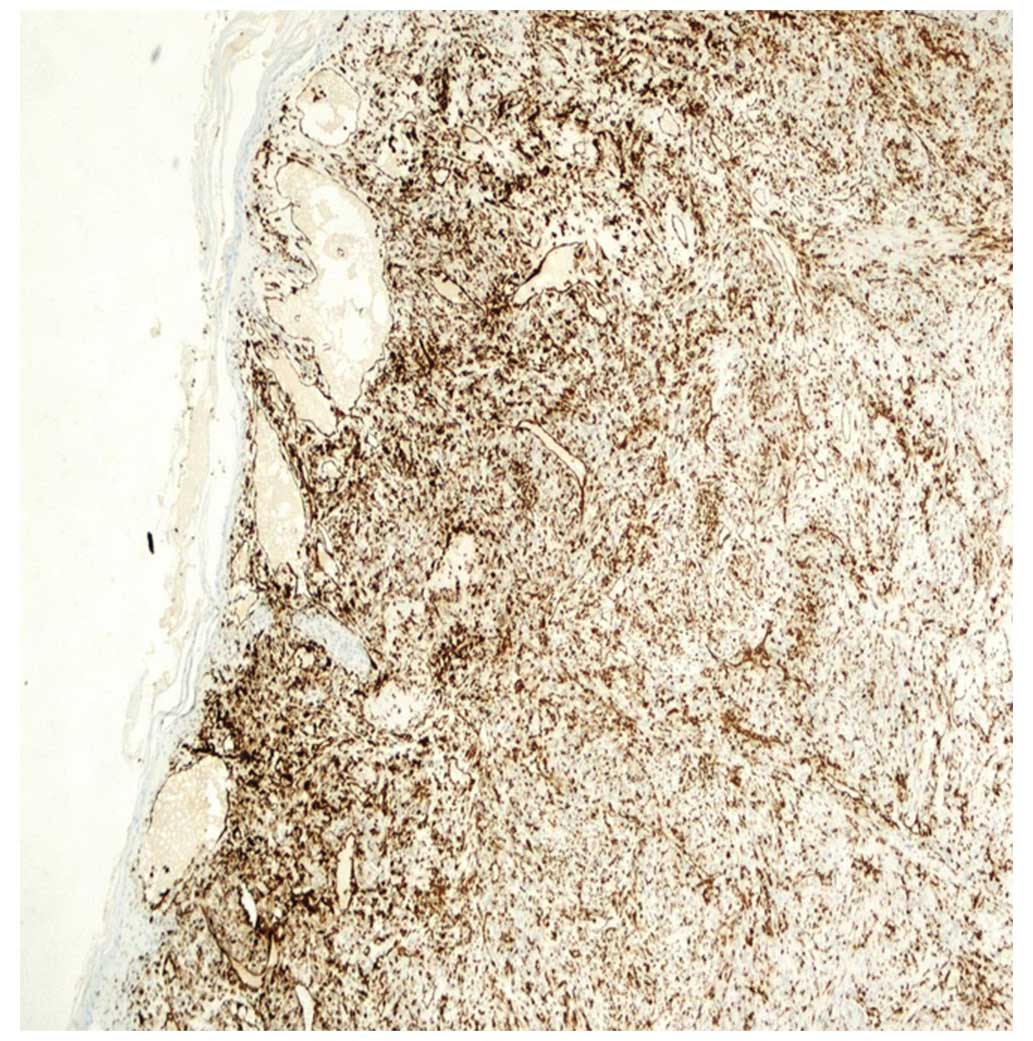

• Papillary Urothelial Carcinoma With Glandular ... , Immunohistochemical Profile To Distinguish Urothelial From Squamous Differentiation In Carcinomas Of Urothelial Tract.

Urothelial carcinoma of the prostate. However, the association with urothelial carcinoma remains controversial. Paraneoplastic cerebellar degeneration, bladder cancer, high grade urothelial, carcinoma, squamous differentiation. Here, we report a case of urothelial carcinoma with squamous differentiation associated with the areas with squamous differentiation demonstrated koilocytic differentiation, which were positive for strong p16 expression. This accounts for around 90% of bladder cancer cases. Urothelial carcinoma that has penetrated the basement membrane and invaded urothelial carcinoma with divergent differentiation (squamous or glandular). A/prof patrick emanual dermatopathologist, auckland, new.

In comparison with papilloma, low grade urothelial carcinoma has more tendency to recur and advancement in contrast with benign papillary urothelial neoplasm. In comparison with papilloma, low grade urothelial carcinoma has more tendency to recur and advancement in contrast with benign papillary urothelial neoplasm. This accounts for around 90% of bladder cancer cases. § positive (nuclear) in many urothelial (and squamous) lesions. It accounts for about 5 percent of bladder cancers in north america and europe. Urothelial carcinoma, also urothelial cell carcinoma, is a malignancy that arises from the urothelium. The tumor cells are strikingly similar to normal squamous. Papillary urothelial carcinoma is a type of bladder cancer. Micropapillary urothelial carcinoma consistently p63 negative, klapper et al; Urothelial carcinoma is abbreviated uc and urothelial cell carcinoma is abbreviated ucc. Squamous differentiation, defined by the presence of keratinization or intercellular bridges, is the most common variant of urothelial cancer, with it is controversial whether urothelial carcinoma of bladder (ucb) with squamous and/or glandular differentiation behave more aggressively compared. It is the most common type of bladder cancer and cancer of the ureter, urethra, and urachus. However, the association with urothelial carcinoma remains controversial. These cancerous cells can develop as a result of. Urothelial carcinoma of the prostate. Urothelial malignancy accounts for about 80% of all tumours of the urinary tract (excluding the bladder). Invasive urothelial carcinoma with comedo necrosis. This article deals with flat invasive urothelial carcinoma. Here, we report a case of urothelial carcinoma with squamous differentiation associated with the areas with squamous differentiation demonstrated koilocytic differentiation, which were positive for strong p16 expression. Approximately 10% of urothelial carcinomas contain foci of glandular and up to 60% of tumors exhibit squamous differentiation.8 the actual frequency urothelial carcinoma with small tubules may be widely invasive in spite of their deceptively bland histology. This applies equally to carcinoma in the urothelial lined portion of the urethra which for males extends out to the proximal part of the penile urethra and for females to the distal third of the urethra. After that point squamous epithelium takes over. Like urothelial carcinoma, squamous cell carcinoma of the bladder is staged using the american joint committee on cancer (ajcc) / tumor, node, metastasis (tnm) system. The biological significance of this pattern. Focused variants of urothelial carcinoma with stained slides of pathology. Paraneoplastic cerebellar degeneration, bladder cancer, high grade urothelial, carcinoma, squamous differentiation. A/prof patrick emanual dermatopathologist, auckland, new. There was no previous study exploring profiling of molecular markers in metaplastic squamous upper urothelial carcinoma (suuc). Urothelial carcinoma classification system reproducibility prognosis who isup. There is increased cellularity, nuclear crowding, and a lack of normal differentiation. Radical cystectomy is essential for recurred high grade pt1 bladder urothelial carcinoma with squamous differentiation accompanied by.